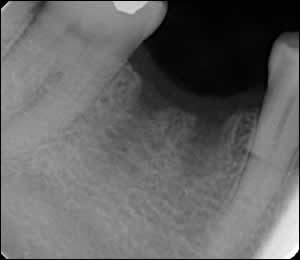

Fig 2: The tooth was extracted